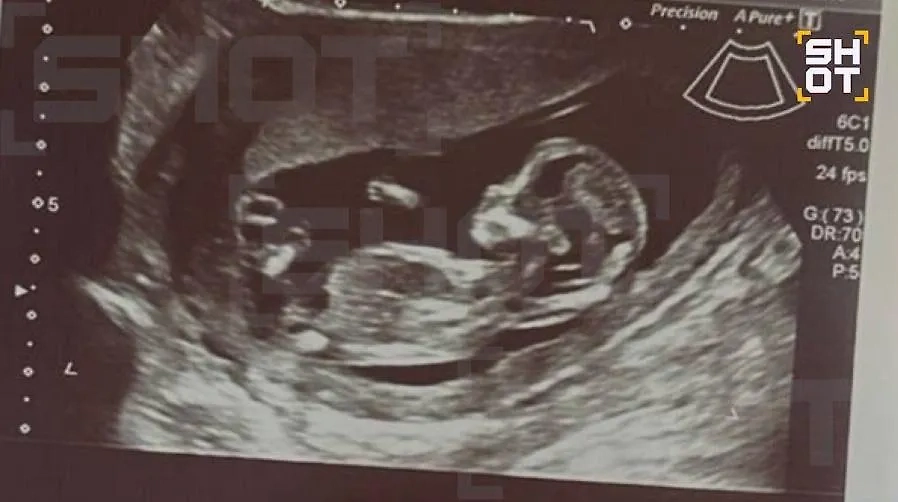

Россиянка лечилась от бесплодия, но забеременела после пластики груди. Фото © SHOT

Врач акушер-гинеколог, которого цитирует SHOT, отметил, что хирургические вмешательства и приём некоторых препаратов на столь ранних сроках могут быть опасны для плода, вплоть до развития тяжёлых нарушений. Однако, несмотря на все опасения, пока беременность Дианы развивается нормально. Первое обследование показало, что никаких отклонений у ребёнка не выявлено.